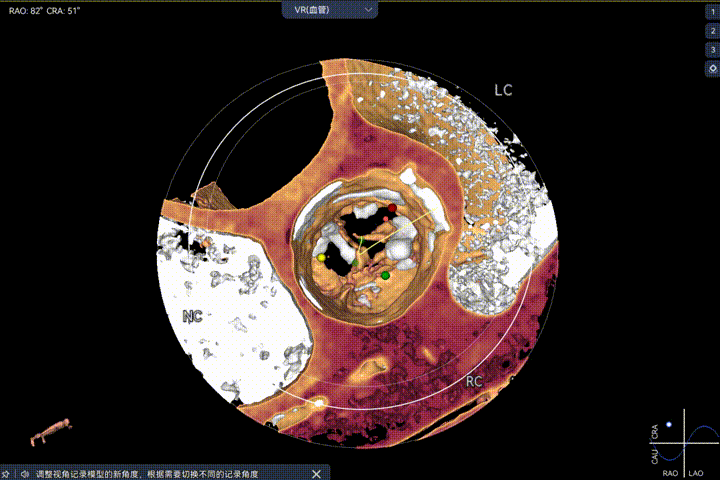

主动脉瓣环周长径21.9mm,小瓣环,LVOT直筒型结构;三叶瓣,左右融合(功能型二叶瓣),瓣叶轻微增厚并重度钙化,钙化主要分布在无冠窦瓣叶边缘及左右交界融合处,瓣上限制较重。

窦部空间适中,STJ内径偏小,升主动脉内径可。

双侧冠脉开口高度可,VTC空间充足,无冠脉风险,双冠内多处钙化,术中评估冠脉支架植入必要性。

外周双侧入路无明显迂曲、直径可容纳20F大鞘通过,双侧中分叉,穿刺需注意。主动脉弓角弓距可,髂总动脉及分支多处钙化,瓷化升主动脉,钙化由升主动脉蔓延至主动脉弓侧壁及弓顶弓底部,有一定卒中和夹层风险。

Step 1.升主动脉情况评估